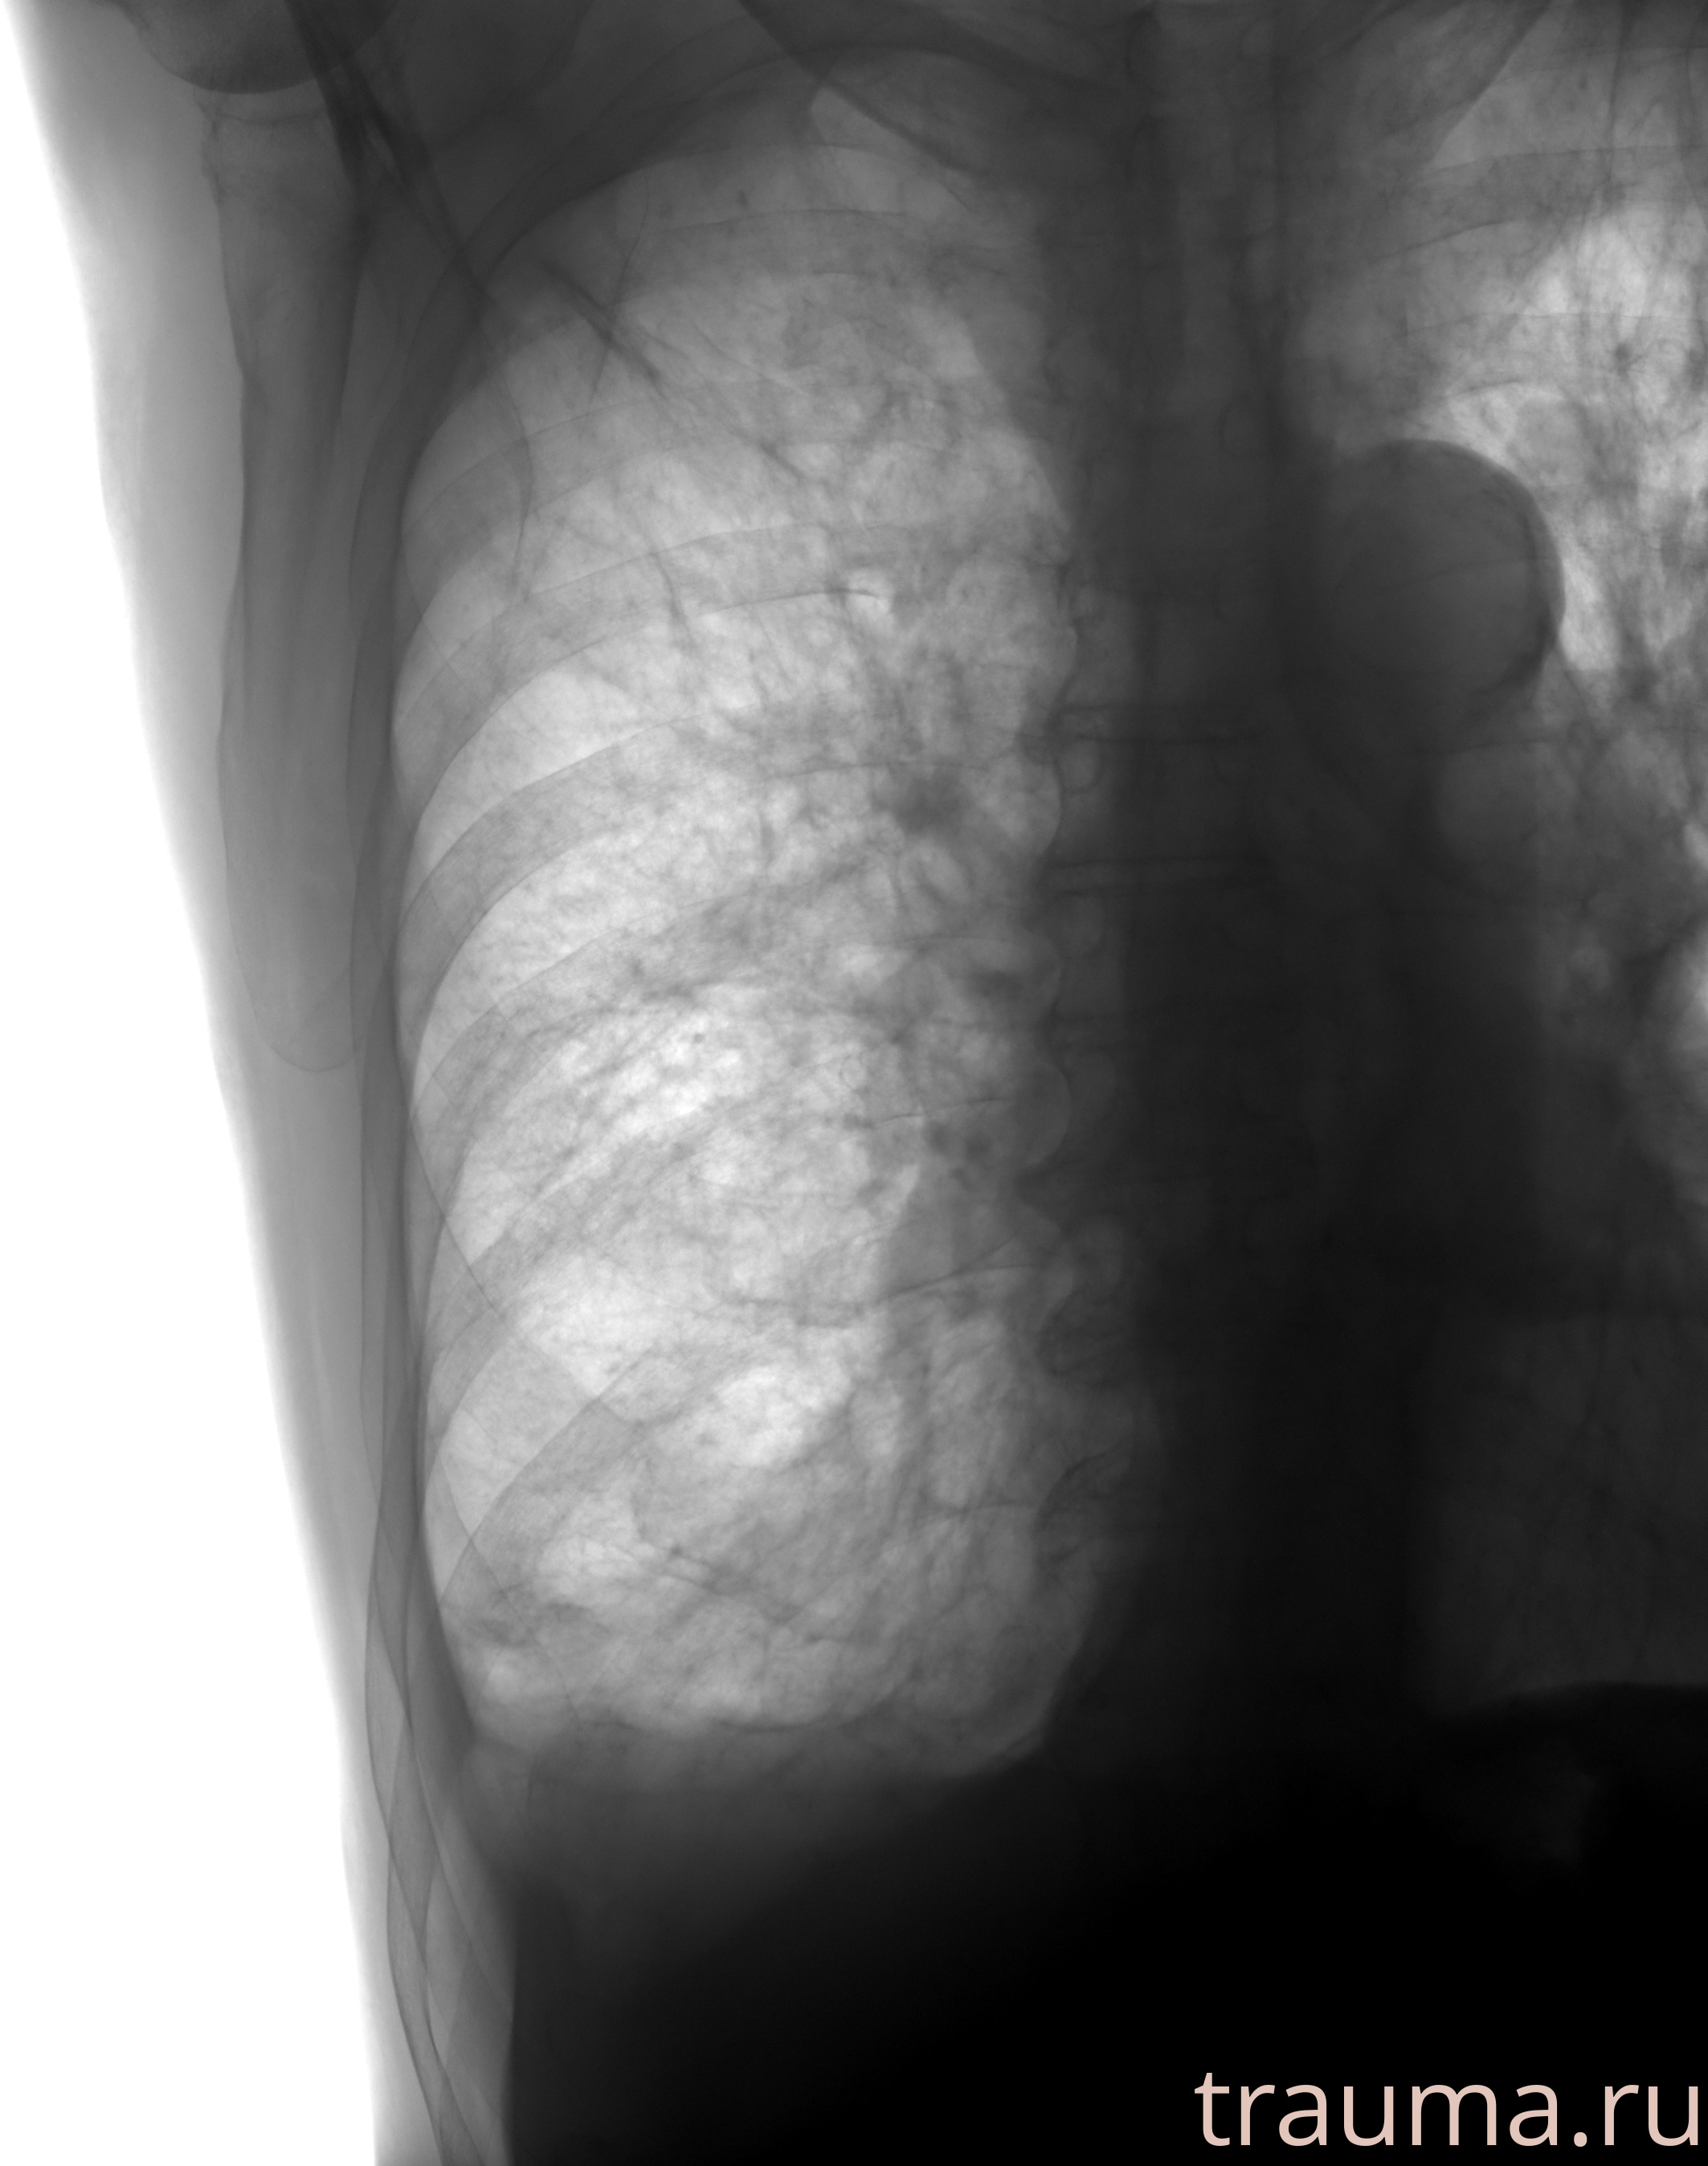

Рентген на дому: по вашему адресу приезжает врач-рентгенолог, травматолог-ортопед с мобильным рентгеновским аппаратом, проводит диагностику травмы или заболевания, делает необходимые рентгенограммы, дает рекомендации по дальнейшему лечению. Получить качественные снимки в домашних условиях возможно благодаря уникальной методике, разработанной МосРентген Центром для института  Склифосовского